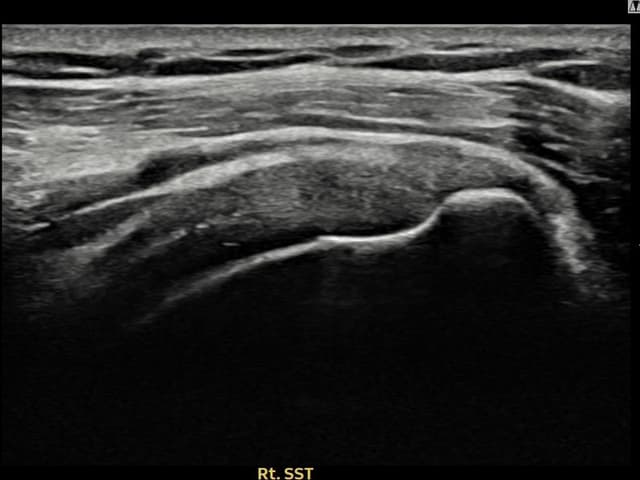

[経過期間: 23.09.01~23.11.03]

[縫縮術] 超音波検査にて右 棘上筋腱 滑液包面側部分断裂(8mm × 4mm (腱厚の約35%欠損))を確認。縫縮術施行後、腱の連続性が回復し、日常生活に復帰されました。